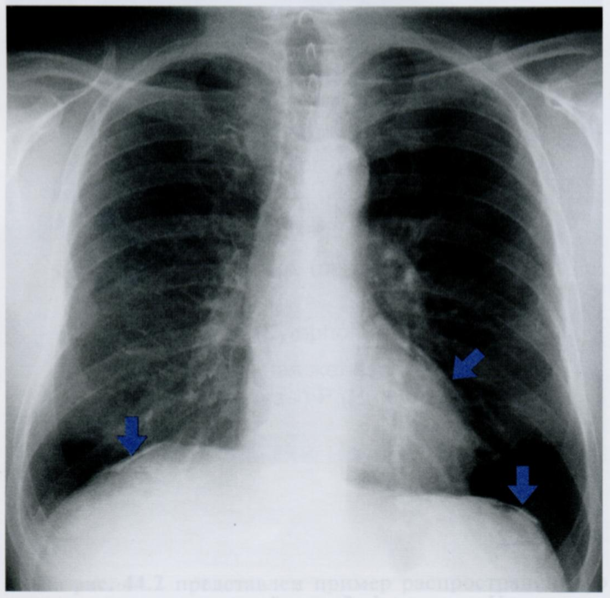

На снимке приведен пример плеврального фиброза в базальном отделе слева (стрелка). Изменения плевры в базальном отделе могут симулировать выпот с небольшим количеством жидкости из-за того, что реберно-диафрагмальный синус выглядит размытым.

Междолевой фиброз (стрелки) с обеих сторон граничит с воздушной тканью легкого и по этому отчётливо определяется в виде линейной тени (второй снимок).

На этой ренттенограмме также имеется утолщение плевры (горизонтальная стрелка) слева в латеральных отделах и сопутствующий выпот в плевральной полости (41).